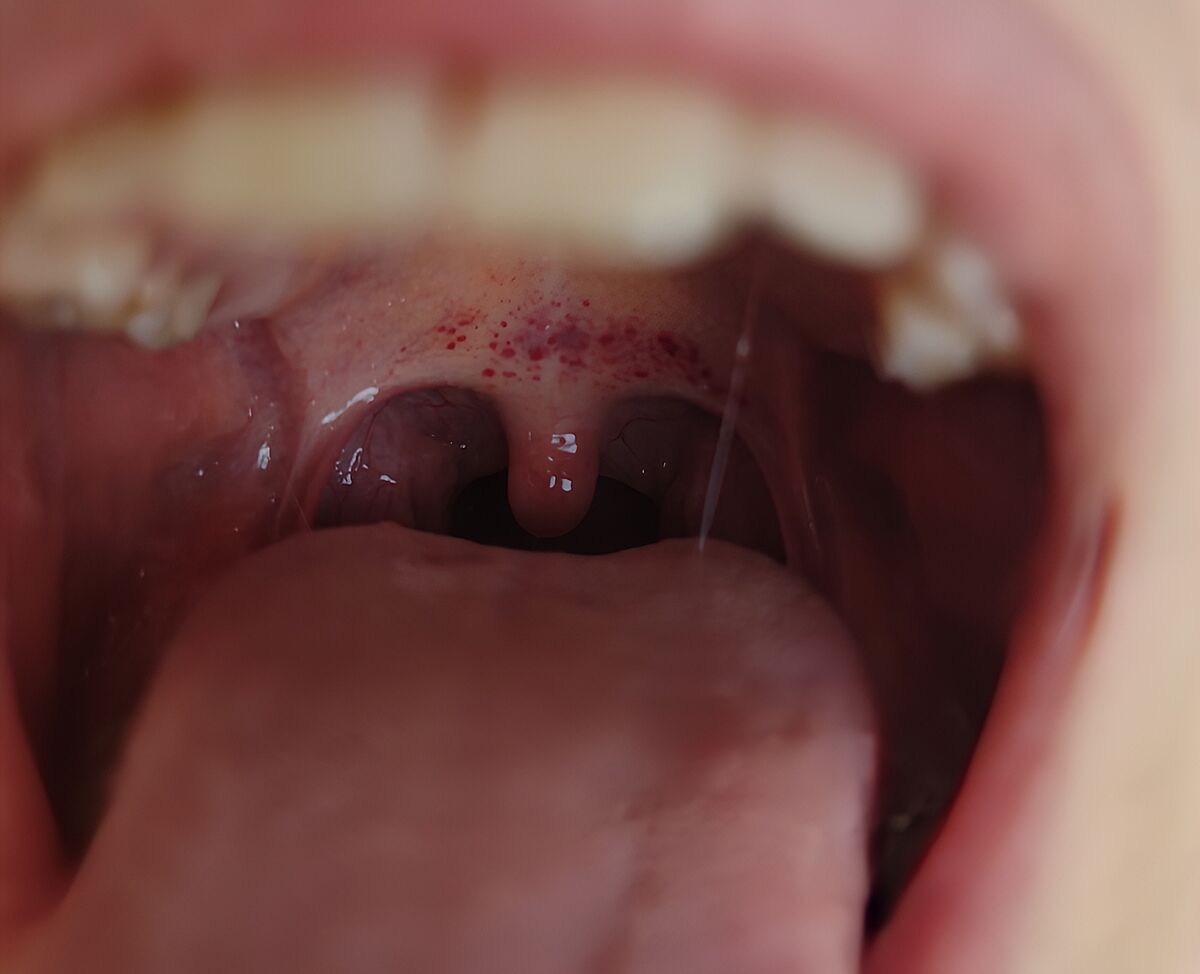

Подивіться на горло, що то таке?

Дитину трохи болить горло, не сильно. Температури немає. Соплів наче також, але так тягне постійно до себе. Кашлю нема.

Чи може бути через те що постійно тягне до себе соплі такий стан горла, чи з чим то зв´язане, треба бути до лікаря чи як?

Так виглядає вірус

Вірус

Ні крапочки лікувати не треба. Лікувати вірус як завжди симптоматично, багато пити теплого (не гарячого)

у мене точно таке щовесни буває, воно нічим іншим себе не виявляє й скоро зникає, може, алергія яка

Жаль, что я поздно тему увидела. Скорей всего, у Вашего подростка вирус, но у детей младших при таком « салюте» на нёбе нужно исключать скарлатину, которая, может протекать и без температуры, но, должна быть пролечена.

Ті штуки ще є, горло не болить, трохи соплі. І все